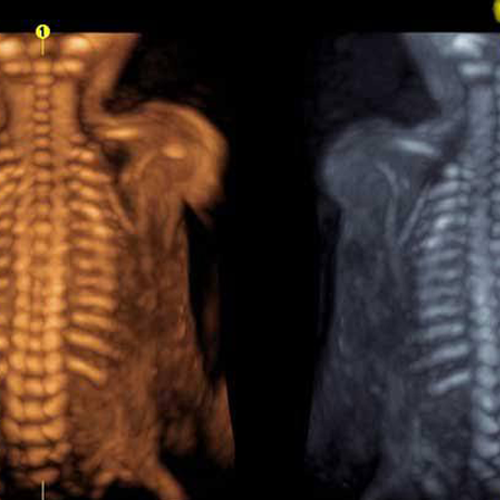

Best Scanning Center In Nakodar